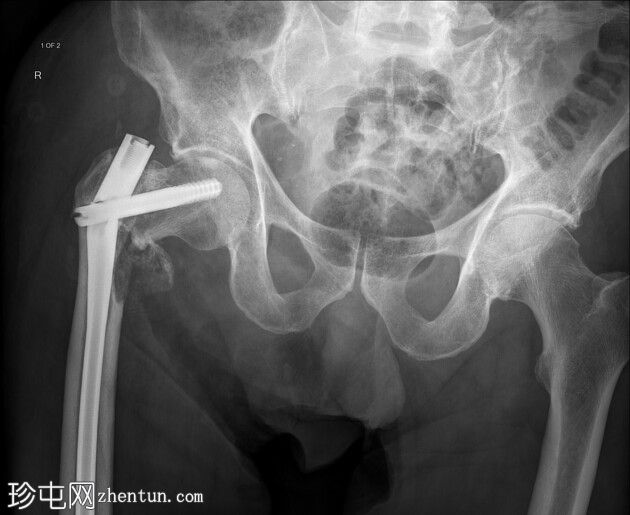

股骨髓内钉断裂

跌倒后右腿缩短且外旋。既往股骨内固定术。已知甲状腺癌伴骨转移。

正面

右侧髓内钉近端骨折(位于拉力螺钉孔位)。

空心髋螺钉组件完好。

股骨转子间骨折延伸至股骨近端转移灶,小转子粉碎。

这是股骨髓内钉断裂的典型案例。由于担心股骨近端溶骨性病变以及患者存在病理性骨折的风险,因此置入了髓内钉。髓内钉断裂是一种罕见但严重的并发症。

在本例中,髓内钉断裂发生在拉力螺钉孔(穿过股骨颈的螺钉)的水平,该水平可能是髓内钉本身较薄弱的部位。靠近该水平的溶骨性病变可能导致了不稳定性和髓内钉的异常应力。